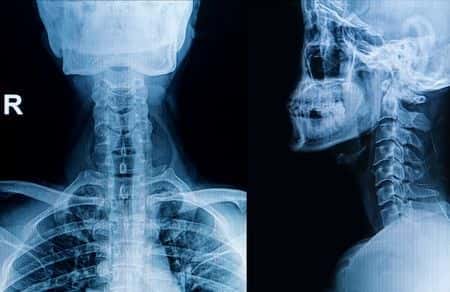

This case involves a male patient, located in West Virginia, who had a past medical history of Cervical myelopathy and multilevel cervical radiculopathy which was suspected to be caused by cervical cord compression. He was recommended for surgery and was taken off his anticoagulants in preparation. The patient underwent a decompressing cervical laminectomy. A hemovac drain was placed in the epidural space. The next day the patient had regained some strength and was sitting up. His anticoagulants (Lovenox were restarted. The patient’s hemovac drain was removed. Three-days later the patient was walking and suffered a sudden loss of sensation in all extremities. The patient had acute respiratory failure and a Code Blue was initiated. He was intubated and transferred to ICU at which point the records state that he was quadriplegic. An MRI of the cervical spine was performed that evening which revealed: “Interval laminectomies from C3-C7 since prior MRI with posterior paraspinous hematoma at midline extending along these levels. STAT CALL, CRITICAL FINDING.” Two-hours later the patient was taken to the OR to evacuate the spinal epidural hematoma. Ten-hours had elapsed since the patient had first showed signs of a neurological complication. Post-operatively, the patient had no movements from the neck down and required mechanical ventilation.